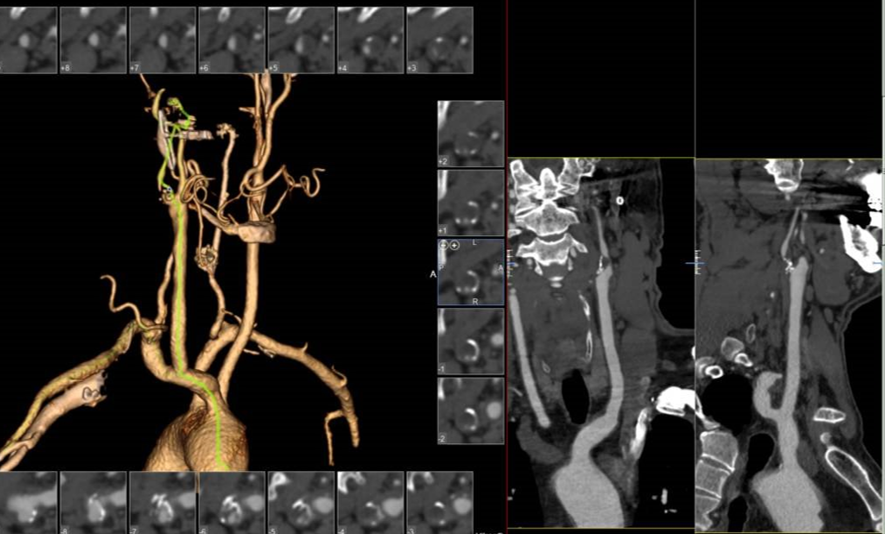

病例1:61岁男性,因双下肢间歇性跛行检查发现双侧颈动脉狭窄,冠脉情况严重,先行两次PCI,后行双侧CAS,先左后右,术后恢复良好。

左侧术前

左侧术后

右侧术前

右侧术后